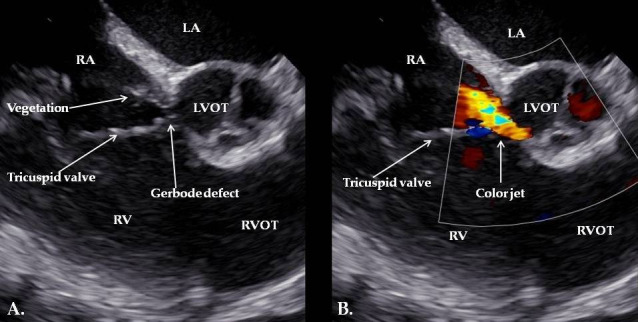

Background and Clinical Significance: Infective endocarditis (IE) is a serious condition with rising incidence, frequently caused by Staphylococcus aureus. However, cases involving rare congenital anomalies such as Gerbode's defect are uncommon. Case Presentation: This report presents the first documented case of IE in a patient with a congenital Gerbode defect complicated by DRESS syndrome-a severe, drug-induced hypersensitivity reaction typically triggered by antibiotics like oxacillin. A 65-year-old woman developed infective endocarditis involving vegetations on the cardiac device lead, the tricuspid valve, and adjacent to a Gerbode defect. The diagnosis was confirmed by positive blood cultures and echocardiographic findings. She received treatment with oxacillin. Subsequently, she exhibited clinical features consistent with DRESS syndrome, including rash, eosinophilia, and multi-organ involvement. Rapid recognition and management, including corticosteroid therapy and antibiotic modification, led to clinical improvement. Conclusions: This case highlights the importance of vigilance for DRESS syndrome in prolonged antibiotic therapy for IE, especially in the context of rare congenital cardiac anomalies. In addition, guidelines are needed to optimize the diagnosis and treatment of this potentially lethal complication.